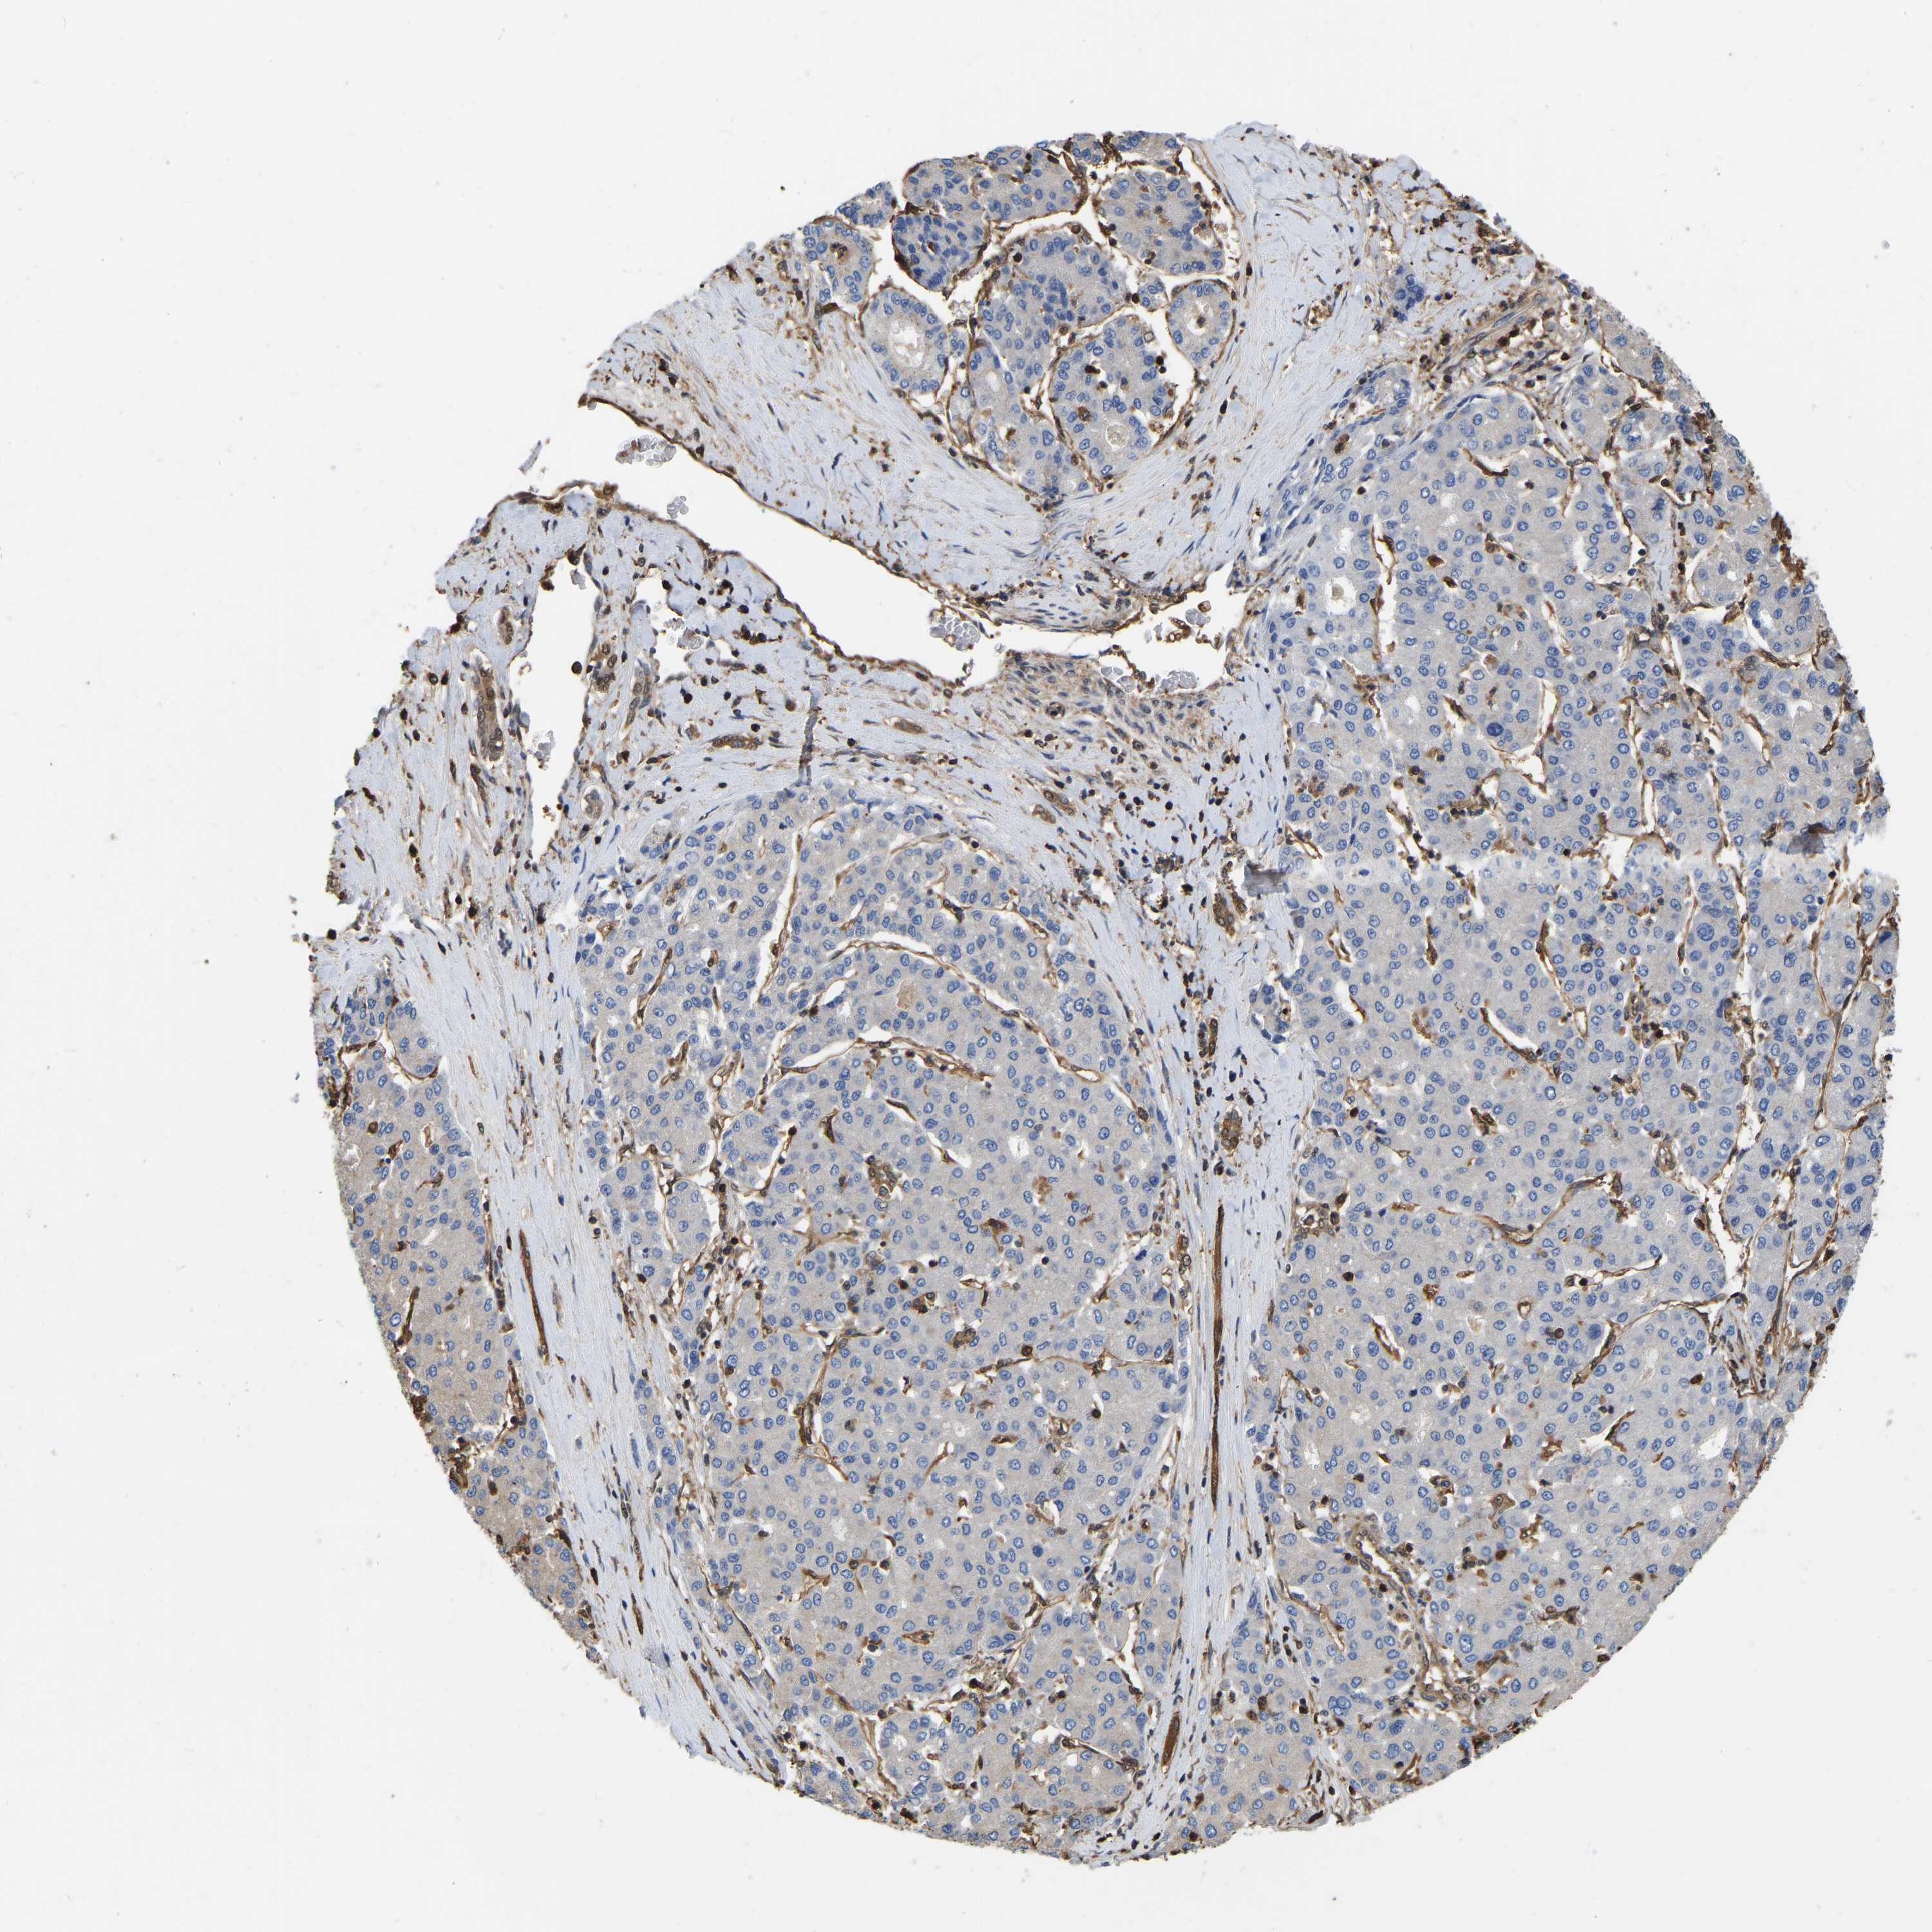

LIVER CANCER - Protein expressioni

A mouse-over function shows sample information and annotation data. Click on an image to view it in a full screen mode. Samples can be filtered based on level of antibody staining by selecting one or several of the following categories: high, medium, low and not detected. The assay and annotation is described here.

Antibody stainingi

Antibody staining in the annotated cell types in the current human tissue is reported as not detected, low, medium, or high, based on conventional immunohistochemistry profiling in selected tissues. This score is based on the combination of the staining intensity and fraction of stained cells.

Each image is clickable and will lead to virtual microscopy that enables deeper exploration of all samples and also displays staining intensity scores, fraction scores and subcellular localization as well as patient and tissue information for each sample.

Antibody HPA019007

Antibody CAB004641

Staining

High

Medium

Low

Not detected

Intensity

Strong

Moderate

Weak

Negative

Quantity

>75%

75%-25%

<25%

None

Location

Nuclear

Cytoplasmic/membranous

Cytoplasmic/membranous,nuclear

Cholangiocarcinoma

Carcinoma, Hepatocellular, NOS